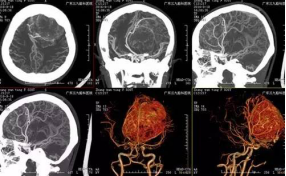

张女士,20岁,因间断头痛伴恶心、呕吐1年余,加重伴右侧肢体麻木1月,为求治疗,来我院就诊。入院后行头颅CT及MR示左侧额部大脑镰旁巨大脑膜瘤,大小约7.8×7.5×7cm,术前CTA提示肿瘤血管丰富,左侧大脑前动脉受挤压明显。由于瘤体太大,为保证患者的手术安全,经科室专家讨论研究决定,择期全麻下为患者行“左侧额部大脑镰旁巨大脑膜瘤切除术”,手术由张良主任主刀完成。经手术、术后康复理疗、物理治疗等系统的治疗后患者症状消失,康复出院。

↑术前检查